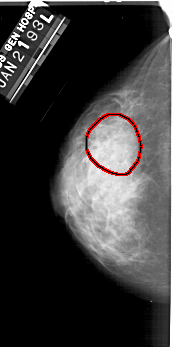

FILE: A_1353_1.LEFT_CC.OVERLAY

TOTAL_ABNORMALITIES 1

ABNORMALITY 1

LESION_TYPE CALCIFICATION TYPE PLEOMORPHIC DISTRIBUTION SEGMENTAL

ASSESSMENT 4

SUBTLETY 2

PATHOLOGY BENIGN

TOTAL_OUTLINES 1

BOUNDARY